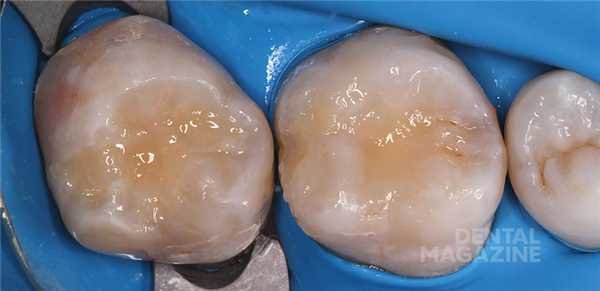

На рисунке 1 показана исходная ситуация.Классический фиссурный кариес зубов 16 и 17. Как и в большинстве подобных случаев, кариозный процесс протекает абсолютно бессимптомно.

После изоляции рабочего поля (рис. 2) и механической отчистки от налета с поверхности зубов снимается ключ bite-силиконом с учетом габаритов клампа (рис. 3) .